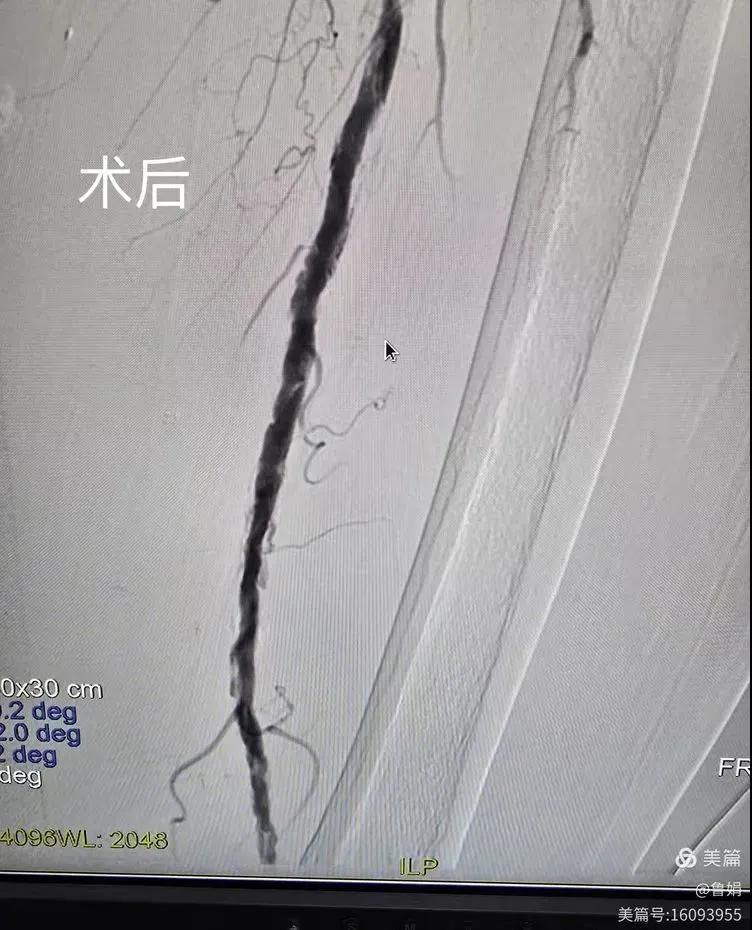

據(jù)悉,該患者,女,73歲,下肢動脈硬化閉塞癥,“以靜息痛,間歇性跛行”入院,CTA評估:股淺動脈,腘動脈間斷性多段重度狹窄,外二科血管外科團(tuán)隊(duì)根據(jù)患者病情,結(jié)合檢查結(jié)果,經(jīng)過科室會診后,決定對該病人行介入治療。手術(shù)由周創(chuàng)業(yè)副主任與北大一院血管外科專家郭宏杰教授聯(lián)合開展,對股淺動脈,腘動脈重度閉塞段行血管開通+藥涂球囊擴(kuò)張成形,術(shù)后狹窄明顯緩解,血流恢復(fù)!